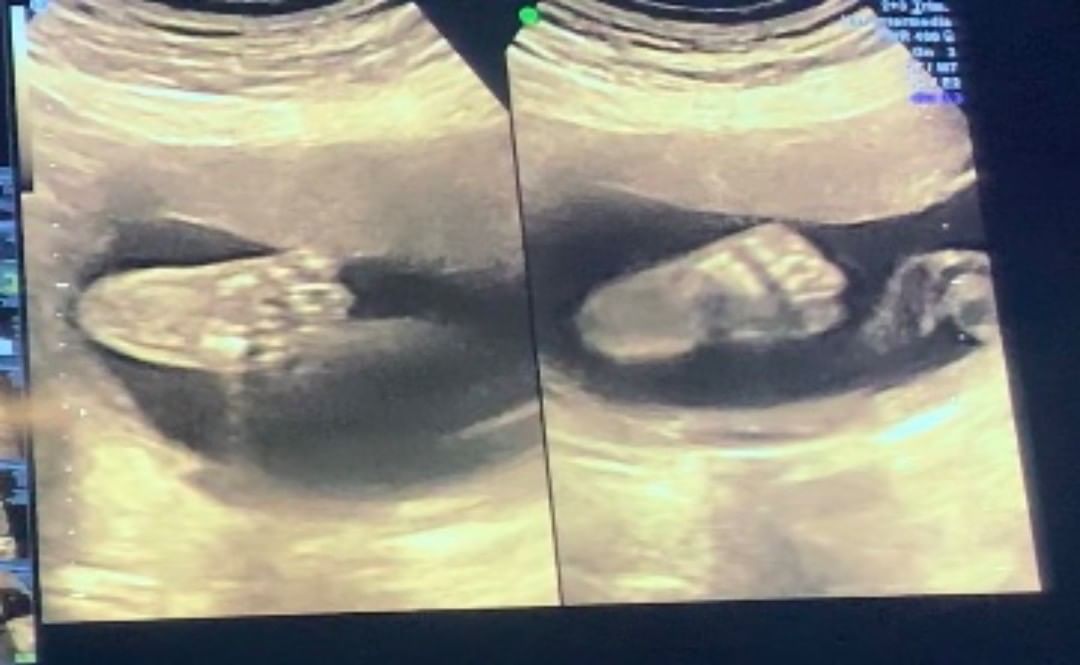

También ha compartido la felicidad de traer alguien al mundo y el hecho de "agrandar" la familia, mostrando las ecografías que le han realizado.

Actualmente, la periodista del matinal de Mega tiene 33 semanas de embarazo y mostró cómo ha crecido su pancita de embarazo.

Sin embargo, también reveló una compleja situación que está viviendo en su embarazo, algo que varias mujeres han pasado en este proceso. "Yo y mis 33 semanas de embarazo! Cada vez queda menos y me emociona demasiado, muchas me preguntan si tengo miedo y la verdad es que no, solo estoy ansiosa por conocerla", partió relatando.

A su vez, tranquilizó a sus seguidores explicando que pese a la diabetes gestacional, su bebé está creciendo súper bien: "El lado positivo, es que mi Amalia está creciendo normal, completamente sana, así que he evitado preocuparme más de lo debido".